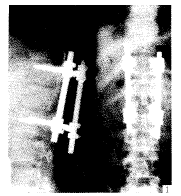

双开窗减压RF内固定治疗胸腰段椎体爆裂骨折

【摘要】 目的 总结治疗胸腰椎爆裂骨折的经验。方法 采用双开窗减压RF内固定治疗胸腰椎爆裂骨折20例。结果 经12~24个月随访,椎体平均前后高度由术前的50.6%和75.4%恢复为术后的91.2%和96.3%。Cobb角由术前平均17.8°恢复为术后平均1°。结论 该方法复位、固定可靠,创伤小,可保留未损伤节段功能,同时保留了后柱的稳定性。